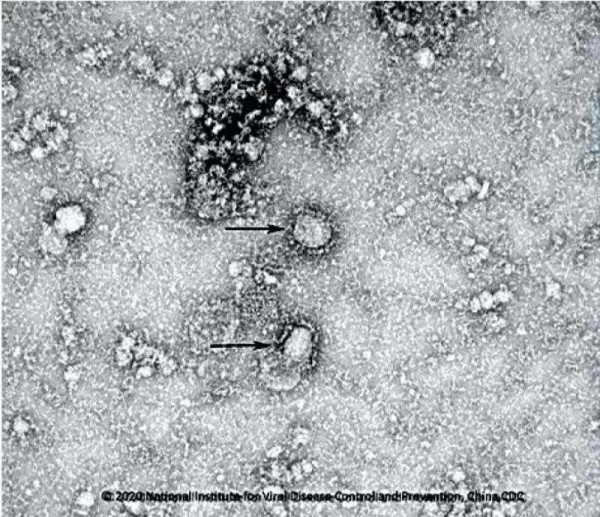

中国疾控中心消息,目前已启动新型冠状病毒的疫苗研发,并成功分离病毒,正在筛选种子毒株。同时,中国疾控中心正在进行新型冠状病毒肺炎的药物筛选。

中国疾控中心消息,中心病毒病所在病毒溯源研究中取得阶段性进展。首次从华南海鲜市场的585份环境样本中,检测到33份样品含有新型冠状病毒核酸,并成功在阳性环境标本中分离病毒,提示该病毒来源于华南海鲜市场销售的野生动物。